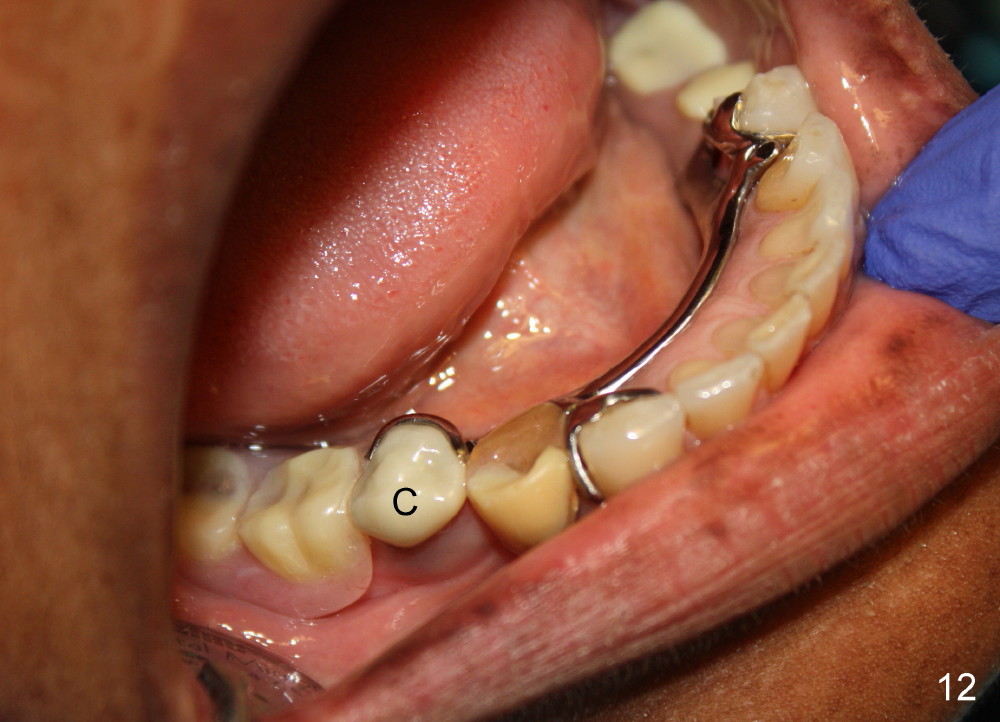

Fig.12,13 show the implant crown in function for 7 months, while Fig.14,15 for 16 months post cementation. In fact, a new RPD has been fabricated with clasp and I-bar (Fig.15 *, as compared to Fig.8,12).